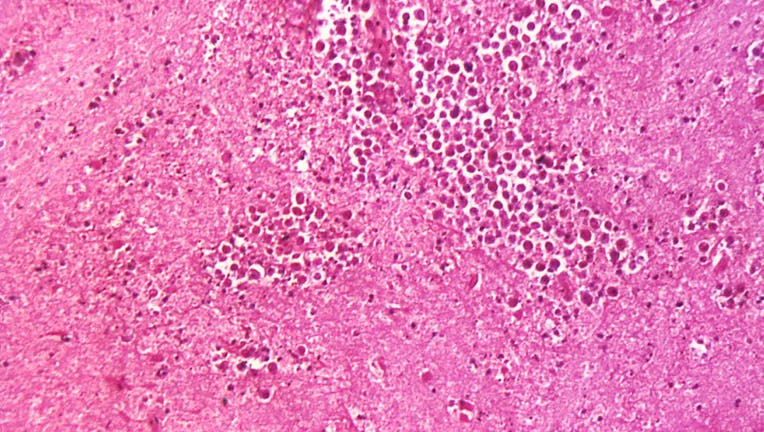

Under a magnification of 125X, this photomicrograph of a brain tissue specimen depicts the cytoarchitectural changes associated with a free-living, Naegleria fowleri, amebic infection. Naegleria fowleri is found in fresh water, soil, thermal discharg